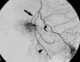

Internal mammary varices